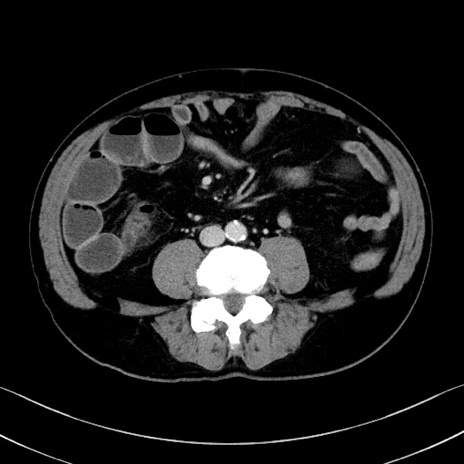

症例35(横断像)

【症例】70歳代 男性

【主訴】腹部膨満、嘔吐

【現病歴】昨日より腹部膨満感出現。本日増悪し、仙痛出現。嘔吐あり、受診。

【既往歴】糖尿病、胆摘後

【身体所見】BP 149/80mmHg、HR 74/min、BT 35.9℃、腹部:膨満、軟、圧痛なし。腸雑音減弱あり。上腹部正中切開瘢痕あり。

【データ】WBC 13500、CRP 1.72